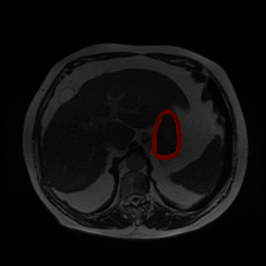

Bias Field Artifact

MRI GMAIMMbench Organ Recognition - Abdomen

Bias Field Artifact - L0 (Original)

L0 (Original)

Question

Observe the MRI image. Can you identify the organ in the highlight area?

A fat B stomach C optic cup D gallbladder E optic disc

Ground Truth: B. stomach